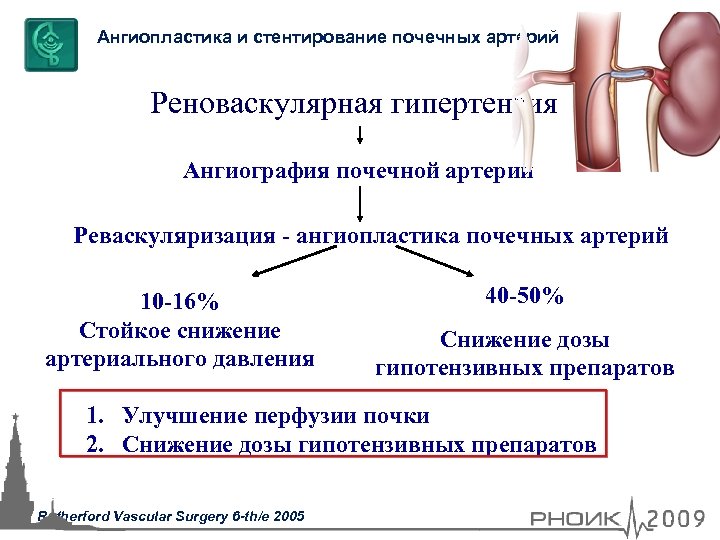

Ангиопластика и стентирование почечных артерий Реноваскулярная гипертензия Ангиография почечной артерии Реваскуляризация - ангиопластика почечных артерий 10 -16% Стойкое снижение артериального давления 40 -50% Снижение дозы гипотензивных препаратов 1. Улучшение перфузии почки 2. Снижение дозы гипотензивных препаратов Rutherford Vascular Surgery 6 -th/e 2005

Ангиопластика и стентирование почечных артерий Реноваскулярная гипертензия Ангиография почечной артерии Реваскуляризация - ангиопластика почечных артерий 10 -16% Стойкое снижение артериального давления 40 -50% Снижение дозы гипотензивных препаратов 1. Улучшение перфузии почки 2. Снижение дозы гипотензивных препаратов Rutherford Vascular Surgery 6 -th/e 2005